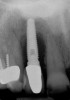

The chief complaint of a 48-year-old woman who presented to her restorative dentist was, “I don’t like the way my implant looks” (Figure 1). This implant had been placed by a previous periodontist and restorative dentist. The patient is now seeking a second opinion. In evaluating this case upon referral to the periodontist, a reddened appearance of the gingival and mucosal tissue encompassing almost the entire facial aspect could be observed. In addition, the radiographs demonstrated a 5-mm diameter implant in place with a deciduous cuspid in the place of No. 11. Deep probing depths were noted around the facial aspect of the implant, and threads could be detected under the tissue.

In evaluating the options, it was decided that the implant placed was too large and that the deciduous cuspid site could be used for a single implant as an abutment for a cantilevered pontic to restore the missing lateral incisor in a more esthetic manner. The goal the treatment was to augment the lateral incisor site in order to bring the facial tissue level more coronal (Figure 2 through Figure 11).